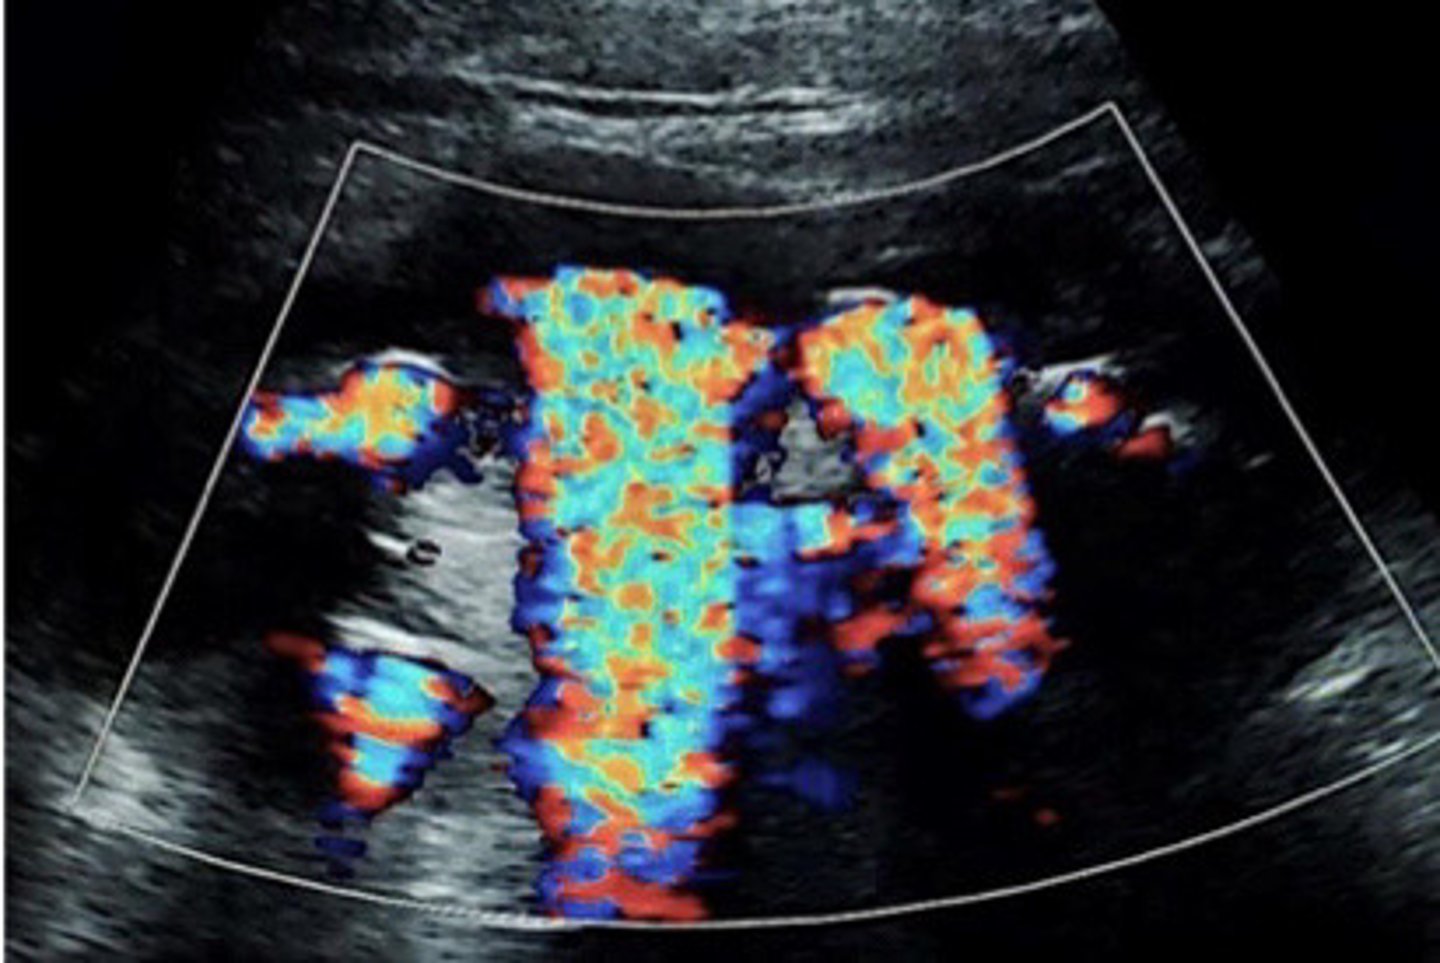

Stone now identified with the twinkle artifact

What does this image show

<p>What does this image show</p>

Twinkle artifact from staghorn calculi

Colour reverberation

What is the twinkling artifact

Colour or power Doppler

What mode do you have to use in order to be able to see the twinkling artifact